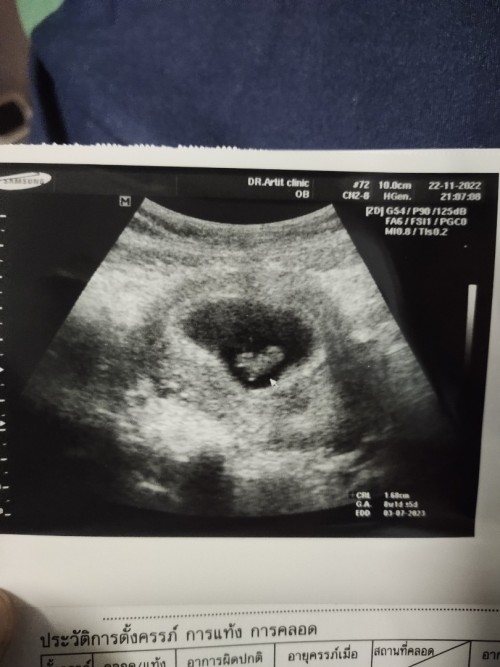

9 weeks 3 วันค่ะ หมอว่าตัวน้องเล็กมากเเต่ยังไม่รู้เพศค่ะ

Post reply image